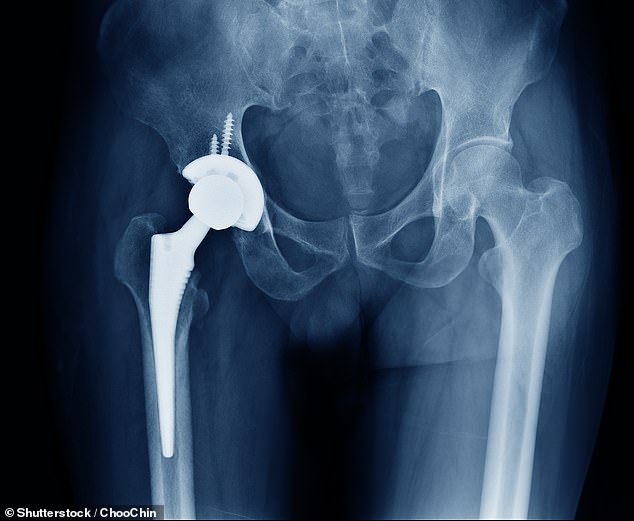

Bone cement, a seemingly simple material, plays a vital role in orthopaedic surgery. It acts like a strong grout, filling the gap between metal implants and bone to create a stable bond that keeps the joint in place. Some formulations include antibiotics, crucial for preventing infections during high-risk procedures or revision surgeries where previous implants have failed. Without this cement, surgeons may be forced to use alternative methods that are less reliable or delay operations until supplies are restored. The issue is not just about a single product—it's about the intricate web of supply chains that sustain modern healthcare.